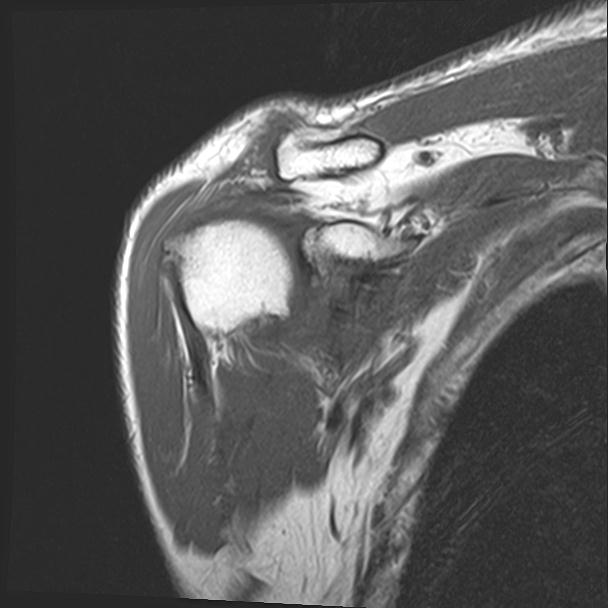

60058 3/9 11/4 右肩 2R+MRI 73歳男性 肩腱板損傷